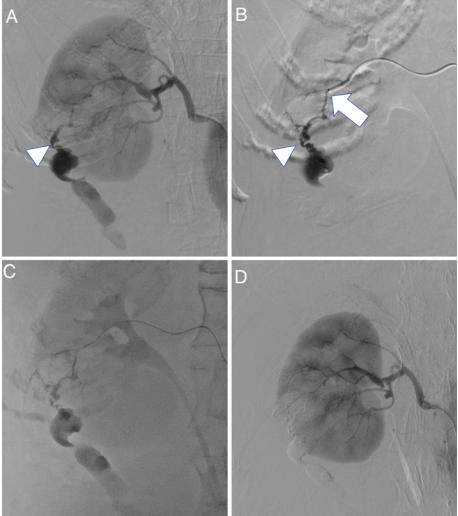

4-F血管造影导管(RC-09;Medikit, Tokyo, Japan)经右股动脉插入右肾动脉。血管造影显示,在弯曲的母血管周围有一个微动脉瘤,有大量造影剂外渗(图3A)。1.9-F的微导管通过0.014英寸的微导丝尽可能地进入母动脉(图3B)。NBCA和乙二磺酸油以1:2的比例混合,(33% NBCA),缓慢持续注射,填充微动脉瘤及近端动脉分支的出血点。(图3C)。术后血管造影未见造影剂外渗(图3D)。随访CT证实血肿缩小,出血部位充满NBCA碘化油铸型(图4)。随后的血液检查未发现贫血进展或肾功能恶化。患者于TAE术后14天无并发症出院。

图3、(A)右肾动脉造影显示微动脉瘤外渗大量造影剂(箭头所指)。(B)肾动脉分支选择性血管造影;箭头指向微导管的尖端。(C)将破裂的微动脉瘤和近端动脉分支以1:2比例(33% NBCA)的氰基丙烯酸酯-脂醇混合物栓塞。(D)栓塞后血管造影显示造影剂外渗停止